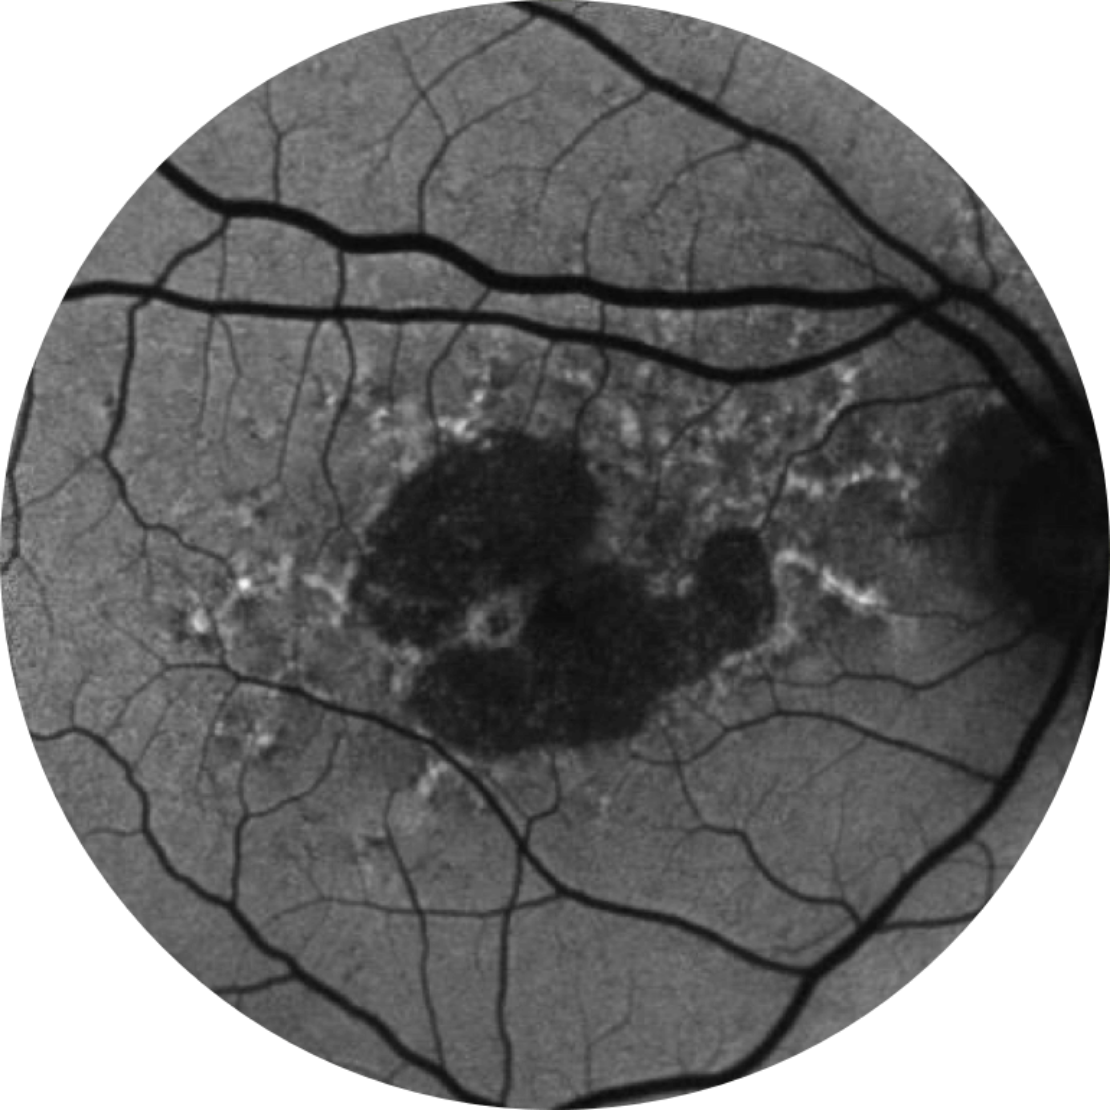

Baseline Year 1

BCVA 20/63+, GA Area 5.18 mm2

Baseline Year 2

BCVA 20/80-2, GA Area 10.39 mm2

Baseline Year 5

BCVA 20/200, GA Area 18.58 mm2

Lesion growth may lead to visual decline.2,16,17

Visual acuity does not strongly correlate with geographic atophy lesion growth. Functional vision declines as lesions grow.15

BCVA = Best-corrected visual acuity

Normal fundus autofluorescence of a retina

Fundus autofluorescence angiography imaging is currently a standard imaging technology to visualise the retinal pigment epithelium (RPE) in geographic atrophy.20